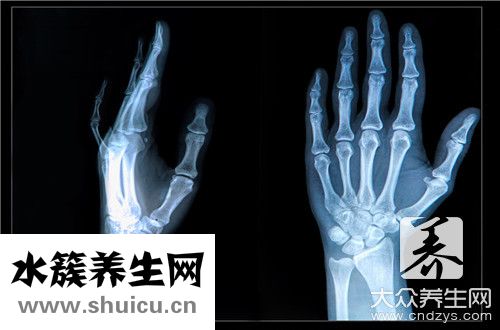

我們的身體有很多關節。 髖骨是其中重要的關節之一,當我們有很大的活動時髖骨在起作用。 當然在日常生活中髖骨也會出現一些意外傷害。 骨折是比較嚴重的意外傷害。 出現髖骨骨折后,需及時治療,手術后仍需認真護理。

髖臼骨折后遺癥嚴重嗎

1. 髖臼骨折是可以治療的,骨折可以愈合,但功能活動怎樣,就要看后期恢復的情況,因為是累及到關節的骨折,容易導致創傷性關節炎.

2. 這部位骨折是個輕難處理的,如果處理不當不及時肯定是會有后遺癥的,不過要是處理及時得當也沒有后遺癥,所以這是個不確定的回答,沒做到及時得當的治療肯定是會有后遺癥的而且后遺癥挺嚴重的。